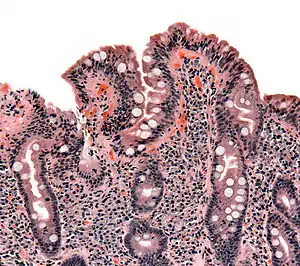

As alterações patológicas clássicas da doença celíaca no intestino delgado são categorizadas de acordo com a Classificação de Marsh:[69][70]

- Estádio 0: mucosa normal

- Estádio 1: infiltração linfocitária intraepitelial superior a 20 por cada 100 enterócitos

- Estádio 2: proliferação das criptas intestinais

- Estádio 3: atrofia parcial ou total das vilosidades intestinais e hipertrofia das criptas[71]

- Estádio 4: hipoplasia da constituição do intestino delgado

A classificação de Marsh, introduzida em 1992, foi posteriormente modificada em 1999 para seis estádios, tendo o estádio 3 sido dividido em três sub-estágios.[72] Os estudos posteriores demonstraram que este sistema nem sempre era fidedigno e que as alterações observadas na doença celíaca podiam ser descritas em um de três estágios — A, B1 e B2 — em que A representa a infiltração linfocitária com aparência das vilosidades normal e em que B1 e B2 descrevem a atrofia parcial ou total das vilosidades.[34][73]